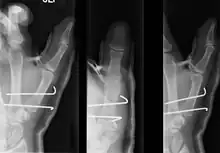

Though these fractures commonly appear quite subtle or even inconsequential on radiographs, they can result in severe long-term dysfunction of the hand if left untreated. In his original description of this type of fracture in 1882, Bennett stressed the need for early diagnosis and treatment in order to prevent loss of function of the thumb CMC joint, which is critical to the overall function of the hand.[4]

- In the most minor cases of Bennett fracture, there may be only small avulsion fractures, relatively little joint instability, and minimal subluxation of the CMC joint (less than 1 mm). In such cases, closed reduction followed by immobilization in a thumb spica cast and serial radiography may be all that is required for effective treatment.[5]

- For Bennett fractures where there is between 1 mm and 3 mm of displacement at the trapeziometacarpal joint, closed reduction and percutaneous pin fixation (CRPP) with Kirschner wires is often sufficient to ensure a satisfactory functional outcome. The wires are not employed to connect the two fracture fragments together, but rather to secure the first or second metacarpal to the trapezium.

- For Bennett fractures where there is more than 3 mm of displacement at the trapeziometacarpal joint, open reduction and internal fixation (ORIF) is typically recommended.

Regardless of which approach is employed (nonsurgical, CRPP, or ORIF), immobilization in a cast or thumb spica splint is required for four to six weeks.